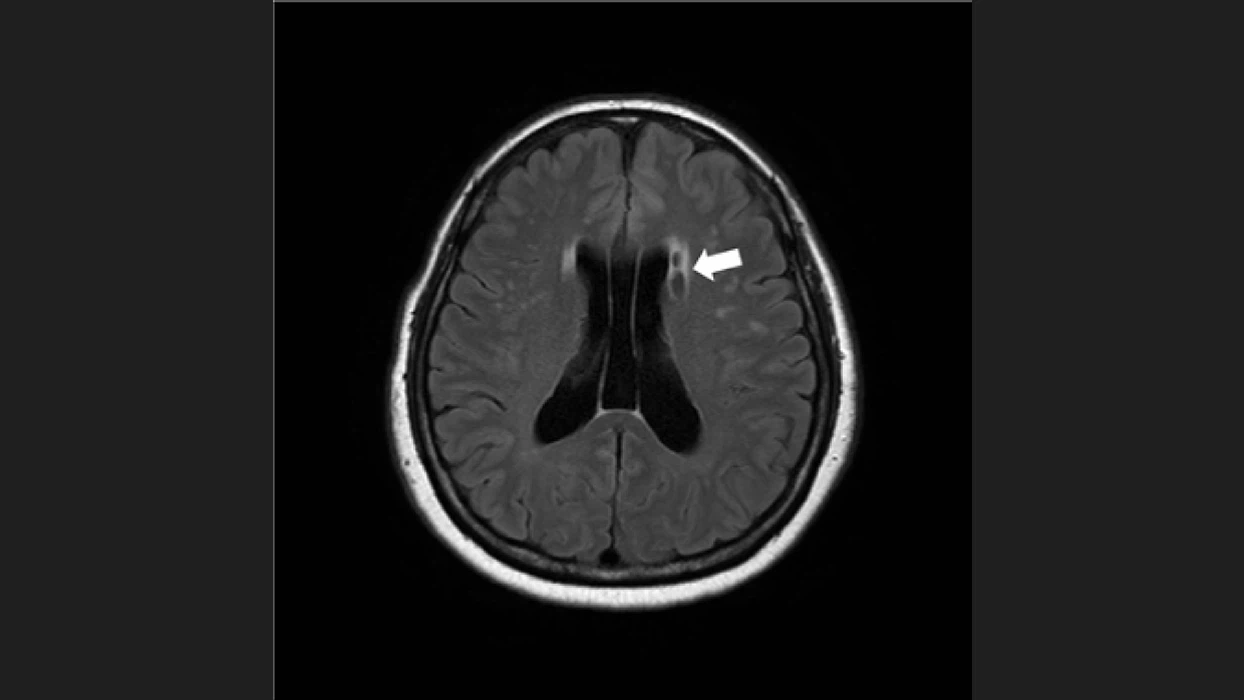

뇌졸중 전조증상 4. 두부 통증

특별한 까닭 없이 갑자기 두부 통증이 자주 발생 하면 뇌졸중의 징후일 수 있습니다. 뇌의 혈관이 파열되며 출혈이 발생하고 뇌 세포가 훼손되며 발생하는 출혈성 뇌졸중에서 제일 흔한 증상이라 합니다. 이러한 출혈성 뇌졸중인 경우에도 극도의 두부 통증이 발생될 수 있다고 하며 강한 두통 증상은 뇌졸중뿐만 아니라 심장질환의 위험성도 의심해 봐야 합니다 때문에 두부 통증과 같이 또 다른 증상이 동반된다면 의료진에게 진료를 받아보는 것이 좋습니다.